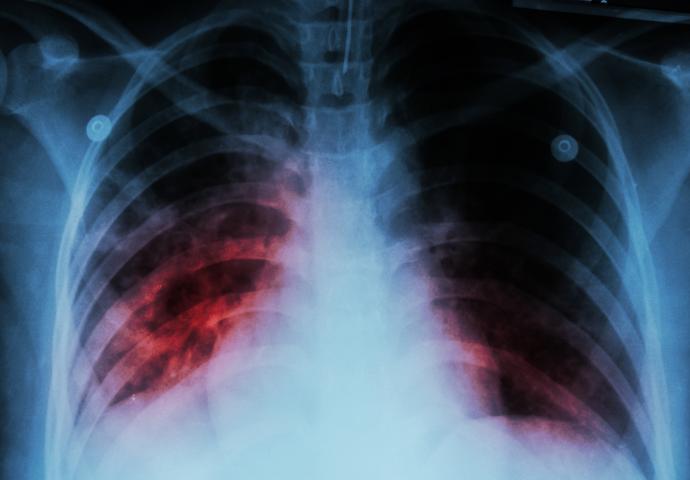

W diagnostyce pojawiają się testy zdolne do szybszego wykrywania oporności na leki, a także narzędzia oparte na sztucznej inteligencji, które analizują obrazy radiologiczne pod kątem wzorców charakterystycznych dla gruźlicy. W połączeniu z programami zdrowia publicznego mogą one skracać czas od wystąpienia objawów do rozpoznania.